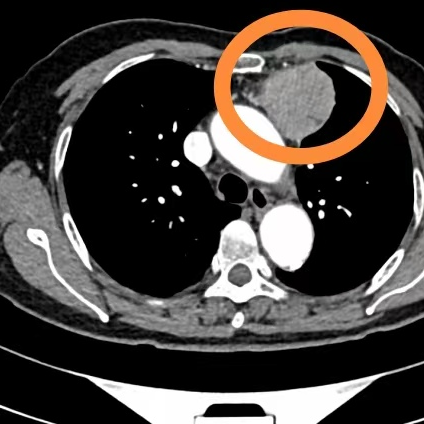

微创,是外科手术发展的永恒主题。自2014年起,我院心胸外科便在自贡创新开展剑突下三孔胸腔镜纵膈肿瘤切除术,后于2016年开展剑突下单孔胸腔镜肺切除及纵隔肿瘤切除术,并凭借该技术荣获 “2018年自贡市引进新技术三等奖” 。

然而,在纵隔肿瘤切除的实践中,团队发现,在常规器械下进行剑突下“单孔”手术,存在暴露困难、操作难度大等挑战。为确保手术患者的绝对安全和效果,科室更多地选择了更为稳妥的剑突下三孔方案。

转机来自技术创新。由四川大学华西医院田东教授发明的 “经皮胸骨天平拉钩” ,很好地解决了这一难题。

这把拉钩像天平一样,稳定、柔和地将胸骨抬起。在剑突下仅一个小小的切口下,拉钩从皮下小孔进入,瞬间为术者创造了一个宽阔、深邃且稳定的操作空间。它就像一双灵巧的 “第三只手” ,牢牢托起胸骨,让以往隐藏在深处的纵隔结构清晰地展现在高清显示屏上,实现“四两拨千斤”。

9月24日,我院胸心外科团队将这一前沿技术应用于临床。

手术中,当天平拉钩轻柔地将胸骨抬起,原本狭窄的纵隔区域豁然开朗,肿瘤暴露充分,周围组织关系一目了然。在清晰的视野保障下,胸心外科主任张远强精准、顺利地完成了肿瘤切除。整个手术实现了“小切口、大视野、精准操作” 的微创理念。